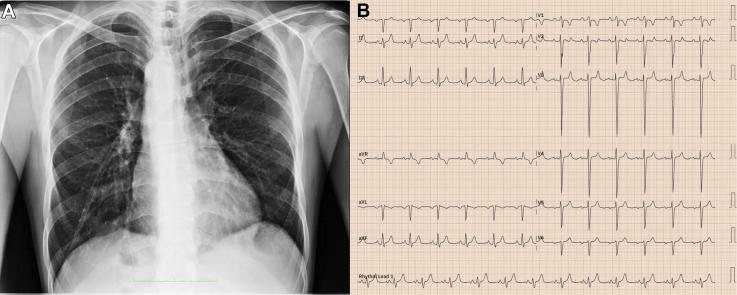

Double-Outlet Right Ventricle in an Adult With a Univentricular Heart and Total Situs Inversus.

Double-outlet right ventricle is a complex conotruncal anomaly in which both great arteries arise predominantly from the right ventricle. The coexistence of total situs inversus and univentricular physiology is exceedingly rare.

CASE SUMMARY

A 38-year-old man presented with severe chronic cyanosis (baseline oxygen saturation 65%), NYHA functional class III dyspnea, and right-sided heart failure. Multimodal imaging (echocardiography, CT, and cardiac magnetic resonance) confirmed total situs inversus, a markedly hypoplastic left ventricle anatomically isolated by a muscular ridge, and double-outlet right ventricle with moderate subpulmonary stenosis. His condition was stabilized medically, but surgical risk was deemed prohibitive owing to his univentricular physiology.

DISCUSSION

This case underscores the critical importance of comprehensive imaging for delineating complex intracardiac anatomy and illustrates how moderate subpulmonary stenosis can temper pulmonary overcirculation, thereby prolonging survival.

TAKE-HOME MESSAGE: Meticulous anatomical definition is essential for managing rare adult congenital heart disease.